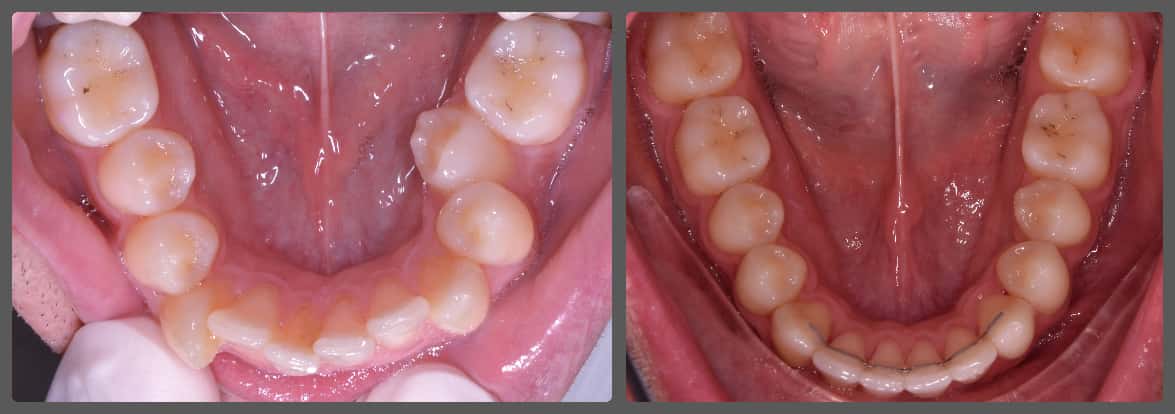

Balázs súlyos alsó torlódása miatt keresett fel magánrendelésemen. A diagnosztikus vizsgálatok során előbbin túl alsó-felső fogívszűkületet, valamint nyitott harapási hajlamot állapítottam meg. Kezelését Pitts21 alsó-felső rögzített fogszabályozó készülékkel kezdtük meg. A nyitott harapási hajlamot a hátsó fogakra helyezett harapásemelővel kontrolláltuk. A torlódott fogaknak tolórugóval és interproximális redukcióval teremtettünk helyet, és intermaxilláris gumihúzással tökéletesítettük a harapást. A fogszabályzó kezelés teljes időtartama alatt Balázs 110%-osan együttműködő volt, ezért 21 hónap alatt sikerült kiemelkedő végeredményt elérnünk.